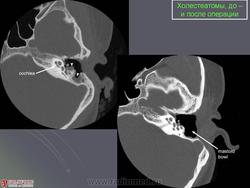

Диагностика холестеатомы представляет определенные трудности. Основными методами выявления холестеатомы последние несколько десятилетий остаются отоскопия (отомикроскопия) и рентгенологические методы (рентгенография в различных укладках и компьютерная томография). Компьютерная томография височных костей позволяет диагностировать холестеатому намного чаще, чем обычная рентгенография, однако степень достоверности данной диагностики остается невысокой, так как плотность холестеатомы практически соответствует плотности грануляционной ткани. Поэтому чувствительность метода КТ в диагностике холестеатомы составляет всего 71% при специфичности 55% [50]. Кроме того, следует учитывать, что указанный метод требует не только дорогостоящего оборудования, но и высококвалифицированных рентгенологов со специальной подготовкой, позволяющей им правильно интерпретировать полученные результаты.

2. Применение компьютерной томографии позволяет повысить степень обнаружения патологического процесса до 90% случаев, однако не позволяет достоверно дифференцировать холестеатому и грануляционную ткань по причине низкой специфичности метода (55%).